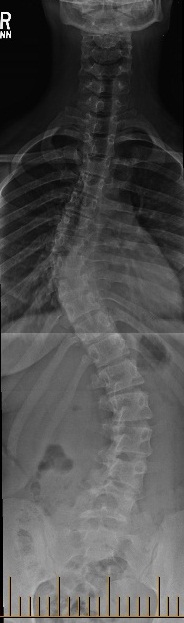

Scoliosis (from Greek: skolíōsis meaning "crooked") is a medical condition in which a person's spine is curved from side to side, shaped like an "s".

On an x-ray, viewed from the rear, the spine

of an individual with a typical scoliosis may look more like an "S" or a "C" rather than a straight line. It is typically classified as congenital (caused by vertebral anomalies present at birth), idiopathic (sub-classified as infantile, juvenile, adolescent, or adult according to when onset occurred) or as neuromuscular, having developed as a secondary symptom of another condition, such as spina bifida, cerebral palsy, spinal muscular atrophy or due to physical trauma.

other posture-related disorders. In rare, severe cases, the curvature can lead to difficulty breathing or heart problems due to a lack of space from the deformed ribcage. A scoliosis is classified based on an angle measurement taken from a full spine x-ray.

// MILD - under 15 degree angle

// MODERATE - 15 to 30 degree angle

// SEVERE - greater than 30 degree angle